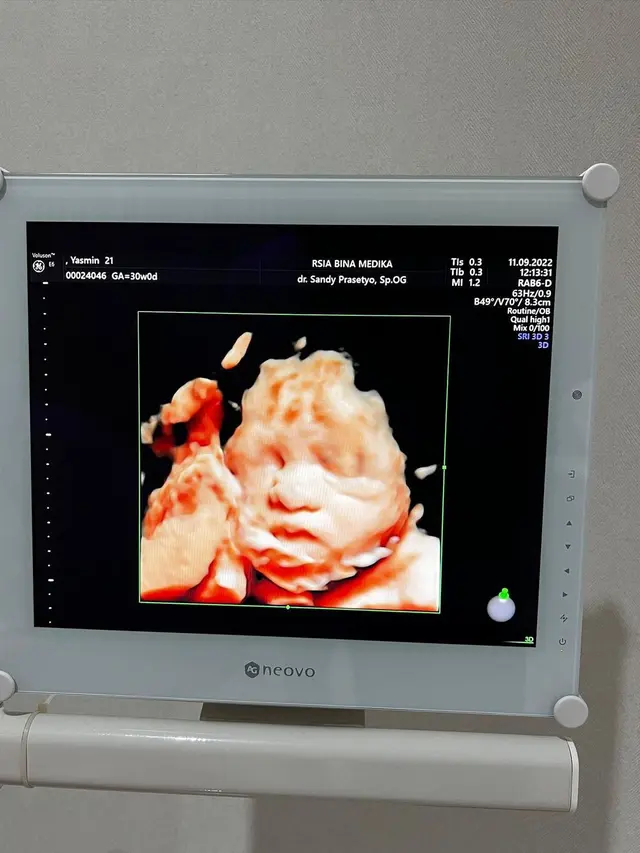

Terbaru, Yasmine membagikan beberapa poretnya bersama suami saat melakukan cek kandungan di instagram pribadinya. Selain itu dia juga memperlihatkan hasil USG 4D calon buah hatinya.

Selanjutnya, Yasmine menyebut calon buah hatinya memiliki wajah yang mirip dengan suami. Kendati begitu, perempuan asal Malaysia ini tidak marah, justru dia minta didoakan agar persalinan nanti berjalan lancar.

"Mukanya baby Z (nama panggilan calon anak) mirip daddy nya banget. Hidung dan bibir ikut daddy ya nak, nggak ada mommy nya. Semoga kamu lahirannya gampang dan sehat selalu," tulisnya.

Melihat unggahan tersebut, netizen lantas setuju dengan apa yang dikatakan Yasmine Ow. Di mana wajah calon buah hati mereka memiliki wajah yang mirip dengan sang ayah.

"Hidungnya kayak bapaknya," tulis netizen. "Masya Allah mirip papanya," timpal netizen lain.